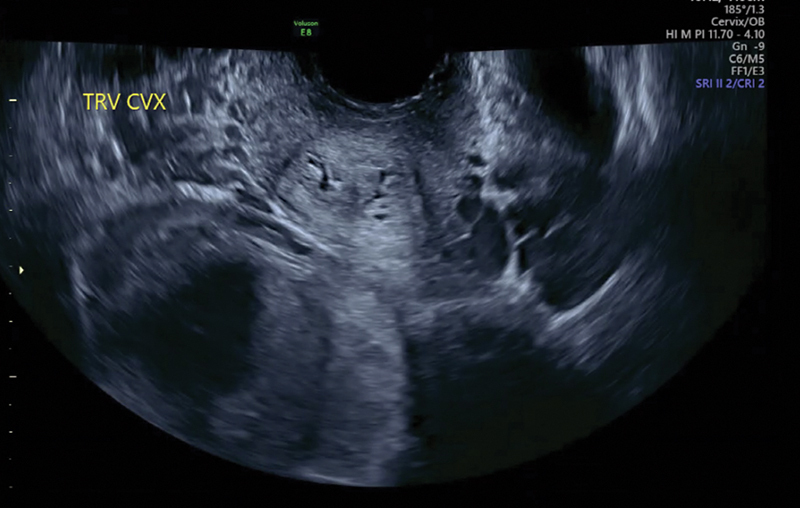

Introduction: A didelphys uterus is a rare Müllerian duct anomaly (MDA) caused by the incomplete fusion of the Müllerian ducts, leading to the formation of two distinct uterine cavities. The occurrence of simultaneous twin pregnancies, with each fetus developing in a separate horn of a didelphys uterus, is estimated at approximately 1 in 1,000,000 cases. This case report describes a rare instance of a spontaneous dichorionic diamniotic twin pregnancy, with one fetus in each horn of a didelphys uterus.

Case description: This is the case of a 35-year-old woman with unilateral renal agenesis who presented with a spontaneous dichorionic diamniotic twin pregnancy, with one fetus in each uterine cavity. This patient's pregnancy complications included intrahepatic cholestasis of pregnancy and rising creatinine levels, leading to a planned cesarean delivery at 36 weeks. The delivery was complicated by intrapartum hemorrhage and the postpartum course was further complicated by sepsis and endometritis.